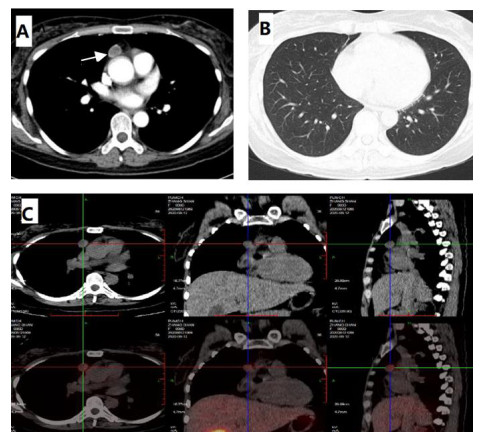

第一次收住院诊疗经过:完善常规生化提示低钾血症、高脂血症,超声心动图:微量心包积液,EF67%。肺通气功能正常。库欣综合征定性定位诊断方面,血总皮质醇(血F)(8AM) 69.6 μg/dL, ACTH(8AM) 664.0 pg/mL, 24 h尿游离皮质醇(24HUFC)2 723.2 μg/24 h,大剂量地塞米松抑制试验(见表 1); 标筛查:AFP 4.6 ng/mL, CA19-9 22.2 U/mL, CEA 3.0 ng/mL, CA125 38.4 U/mL, 细胞角蛋白19片段Cyfra211 6.0 ng/mL, CA242 19.0 U/mL, CA72-4 8.6 U/mL, CA15-3 12.9 U/mL, ProGRP 26.0 pg/mL, NSE 15.4 ng/mL。生长抑素受体显像:前纵隔结节,生长抑素受体高表达灶,考虑神经内分泌肿瘤可能性大;双侧肾上腺增生。(图 1C);垂体平扫+动态增强MRI:垂体后叶短T1信号存在垂体左翼强化减低区,考虑微腺瘤。胸增强CT:前纵隔占位,结合病史,不除外异位ACTH瘤(图 1A);TB细胞亚群11项: %memory T4 78.1%, B% 17.9%, T4% 17.6%, T8% 42.1%, RAT4% 21.9%, NaT4% 21.7%, 28T8% 32.1%, DRT 8% 76.2%, 38T8% 83.0%, T4/T8 0.42%, 垂体前叶功能,甲功1:TSH 0.077 μIU/mL, FT4 1.73 ng/dl, FT3 2.17 pg/mL, GH < 0.05 ng/mL, IGF1 132 ng/mL。FSH 2.13 IU/L, LH 0.26 IU/L, E2(Ⅱ) < 15 pg/mL, T 1.96 ng/mL, PRL 6.9 ng/mL, P 5.31 ng/mL。MEN筛查,GASTRIN 260 pg/m,ProGRP 23.9 pg/mL。降钙素(CT) < 1.5 pg/mL,钙素原PCT 0.23 ng/mL, CK 33 U/L。IPSS+DDAVP兴奋试验示基线时中枢和外周ACTH无梯度(见表 2),结合大剂量地塞米松抑制实验不被抑制,支持异位ACTH综合征,考虑胸腺占位为责任病灶可能。治疗方面,入院后予口服及静脉补钾、螺内酯纠正低钾血症,监测血糖,餐后2 h血糖高,给予胰岛素及口服降糖药后血糖基本达标。患者前纵隔结节考虑为异位ACTH瘤可能大,2020-08-26行VATS胸腺及肿瘤切除术,术后恢复良好,激素替代方案由围术期静脉应用琥珀酸氢化可的松逐渐过渡为醋酸氢化可的松片早40 mg,晚20 mg替代治疗后出院(图 3主要指标趋势及用药情况)。2020-08-31无明显诱因出现发热,体温最高达39℃,当地诊所静点“头孢类抗生素”、口服布洛芬治疗2 d,仍间断发热,并出现站立后头晕,当时血压76/40 mmHg,就诊当地医院,查血常规:WBC 6.01×109/L, NEUT% 85.2%, LYM% 13%; CRP 194.74 mg/L; CMV DNA阳性;胸部CT提示双肺弥漫渗出,考虑“重症肺炎I型呼吸衰竭”于当地重症监护室予以“无创呼吸机辅助呼吸,哌拉西林他唑巴坦、奥司他韦、伏立康唑抗感染,丙种球蛋白免疫支持”。治疗效果欠佳,胸闷、憋气逐渐加重,伴咳少许白色黏痰。2020-09-03就诊本院,考虑重症肺炎收入急诊重症监护病房,第2次收住院诊疗经过:呼吸方面:复查胸CT提示:双肺弥漫炎性改变,双侧胸腔积液并左下肺轻度膨胀不全(图 2A 、B)。予高流量氧疗支持,完善肺泡灌洗液: PCP DNA阳性(+),CMV(+),结合病史、症状、体征及辅助检查证据,考虑肺孢子菌肺炎、巨细胞病毒肺炎、混合细菌感染,头孢他啶1 g/8 h、莫西沙星0.4 g/d、TMP/SMX 3片3次/d,更昔洛韦0.25 g/8 h,呼吸困难逐渐改善,复查CT病灶明显吸收(图 2C 、D)。内分泌方面:考虑EA导致CS术后,激素替代治疗中合并机会性感染,调整治疗:停用口服,给予琥珀酸氢化可的松50 mg/6 h。口服降糖药控制类固醇糖尿病,口服碳酸钙片治疗骨质疏松。原发病方面:结合病理胸腺病灶考虑内分泌来源类癌,恶性程度低,无需放化疗。2020-09-30出院时患者无发热、头晕、纳差、恶心、呕吐、电解质紊乱、低血糖等肾上腺皮质功能不全表现,氢化可的松早40 mg-午20 mg逐渐减量(图 3主要指标趋势及用药情况),激素替代期间TMP/SMX 2片/d预防感染,门诊随诊。

| A:纵隔窗白色箭头提示前纵隔占位1.8×1.6cm;B:肺窗未提示感染感染;C:99mTc-HTOC:前纵隔结节,生长抑素受体高表达灶 图 1 8-13胸部增强CT |

2.2 本例患者的诊疗要点有哪些?定位定性诊断:患者首次入院既表现为高皮质醇血症的体貌(包括脸圆、痤疮、锁骨上脂肪垫、唇上小须等),同时伴有双下肢浮肿及持续的中-重度低钾血症。结合辅助检查特点血皮质醇水平、24 h游离尿皮质醇升高,血皮质醇节律消失,小剂量地塞米松试验未被抑制,考虑库欣综合征定性诊断明确。定位诊断方面,患者外院和本院查血尿皮质醇显著升高的同时ACTH不被抑制,符合ACTH依赖的CS,结合大剂量地塞米松抑制试验未被抑制,垂体动态增强核磁未见明显异常,奥曲肽显像、99mTc-HTOC等影像学均提示前纵隔结节生长抑素高摄取,考虑异位ACTH综合征明确,犯罪病灶在前纵隔,本病常见于异位肿瘤分泌促肾上腺皮质激素,如肺癌、胸腺瘤、支气管类癌、消化道和卵巢肿瘤等,通常病情进展快,ACTH升高明显,往往存在严重低血钾、代谢性碱中毒等。